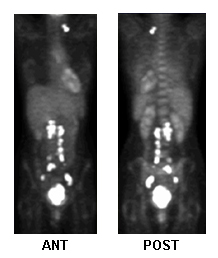

Fluorodeoxyglucose-PET for treatment planning, metastatic activity

From the collection of Neil S. Horowitz, MD; used with permission